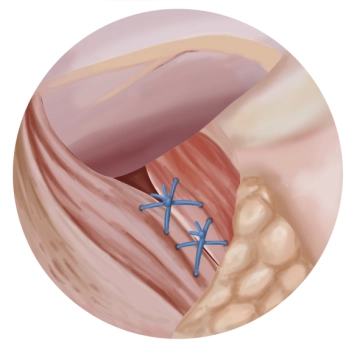

Hintere Hiatoplastik

![Hintere Hiatoplastik]()

Toneinstellungen Es erfolgt eine hintere Hiatoplastik mittels zweier Z-Nähte (geflochtener, nicht resorbierbarer Faden Stärke 1). Der Duchtritt für den Ösophagus muss dabei ausreichend weit und gut durchgängig bleiben.

Tipp: Zur Vermeidung einer Einengung des terminalen Ösophagus durch die Hiatusplastik wird empfohlen, einen Magenschlauch Charrière (Ch) 40 als Kalibrierungsbougie transoral einzuführen.